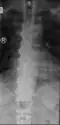

Ectopic calcification and new bone formation in diffuse idiopathic skeletal hyperostosis (DISH)